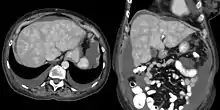

CT appearance of liver in congestive hepatopathy, sometimes referred to as a nutmeg liver. Due to congestion, contrast does not flow through the liver in a normal manner. Axial and coronal images in the portal venous phase.

Increased pressure in the sublobular branches of the hepatic veins causes an engorgement of venous blood, and is most frequently due to chronic cardiac lesions, especially those affecting the right heart (e.g., right-sided heart failure), the blood being dammed back in the inferior vena cava and hepatic veins. Central regions of the hepatic lobules are red–brown and stand out against the non-congested, tan-coloured liver. Centrilobular necrosis occurs.[2]

Macroscopically, the liver has a pale and spotty appearance in affected areas, as stasis of the blood causes pericentral hepatocytes (liver cells surrounding the central venule of the liver) to become deoxygenated compared to the relatively better-oxygenated periportal hepatocytes adjacent to the hepatic arterioles. This retardation of the blood also occurs in lung lesions, such as chronic interstitial pneumonia, pleural effusions, and intrathoracic tumors.